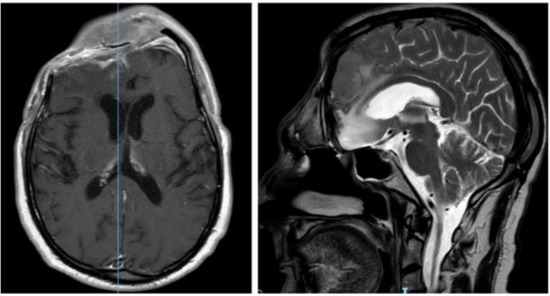

2. Case Report

| Present case | Rectus femoris and fascia lata (1) | Atypical meningioma (1) | Sphenoidal planum (1) | - |